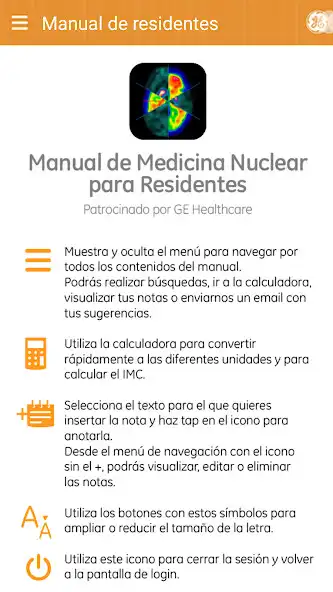

Como funcionalidades destacadas de la App se incluyen realizar bsquedas por captulo o en todo el contenido del manual y la posibilidad de insertar tus propias notas en cualquier parte del texto para su posterior consulta.

Recent changes: - Incluimos micro videos tutoriales para sacar el máximo partido a la App: "Cómo utilizar las notas" y "Cómo compartir notas entre sus dispositivos"

- Nueva funcionalidad de compartir notas entre los dispositivos de un mismo usuario.

- Optimización en el funcionamiento de la calculadora de conversión de datos para que sea bidireccional.

- Nuevo buscador con posibilidad de localizar sub/sup índices entre el texto.